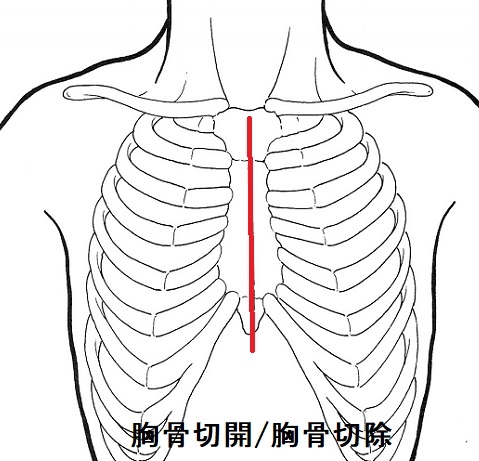

甲状腺手術で首の辺を切開するのは当然ですが、胸骨切開(全切開、部分切開)/胸骨切除が必要な時もあります。

- 縦隔進展する巨大甲状腺腫(縦隔内甲状腺腫 )

- 甲状腺癌の転移・浸潤が胸骨の所まで及ぶ

などの場合です。胸骨切除は大胸筋皮弁形成が必要となり、炎症による胸水貯留がおきる場合もあります。